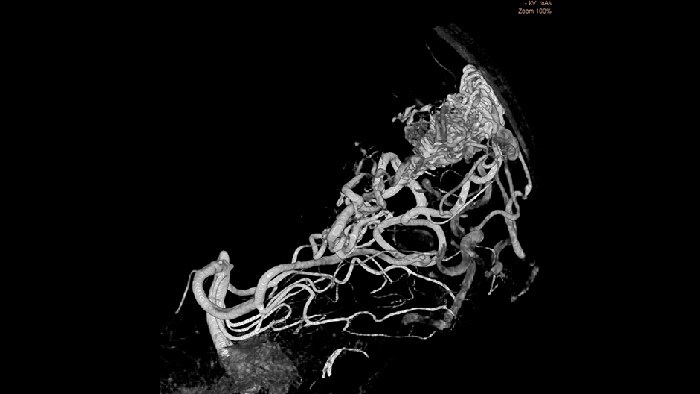

Clinical solutions for monitoring and treating AVMs, AVFs and other malformations

During neuro interventions, the goal is to see clearly, while managing safety for all involved. The Azurion system geometry combines speed and sophistication with the introduction of Image Beam Rotation, allowing 135-degree rotations on the frontal arm, giving you the most flexible Philips biplane system to date, providing optimal access to the patient’s head-end. Seamlessly control all compatible applications from a single touchscreen at tableside to help make fast, informed decisions in the sterile field. Simplifies 3D acquisition so any clinical user3 can easily perform 3D imaging.